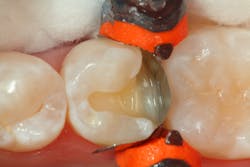

A total-etch technique is used, and the entire prep is etched with 35% phosphoric etch (Vococid, Voco). Once rinsed and lightly dried, a universal bonding agent (Futurabond U, Voco) is applied, air-dried, and light-cured.

A thin layer of flowable composite (GrandioSO Light Flow, Voco) is applied to the most apical portion of the proximal box to ensure there are no voids in this caries-prone area (figure 3).

The restorative composite (GrandioSO, Voco) is placed and sculpted to its initial form and light-cured.